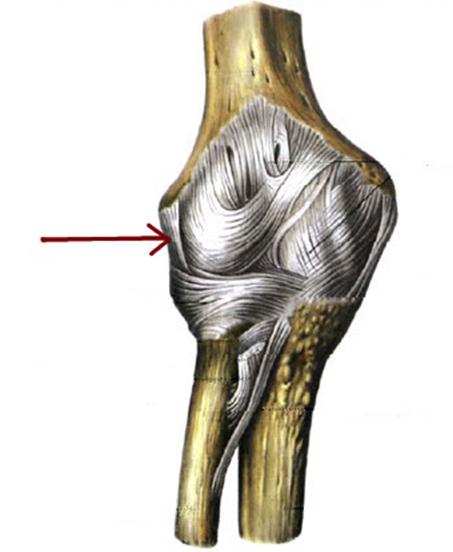

S: Стрелка указывает на art. ### (латинский язык).

+:humeri

+:Humeri